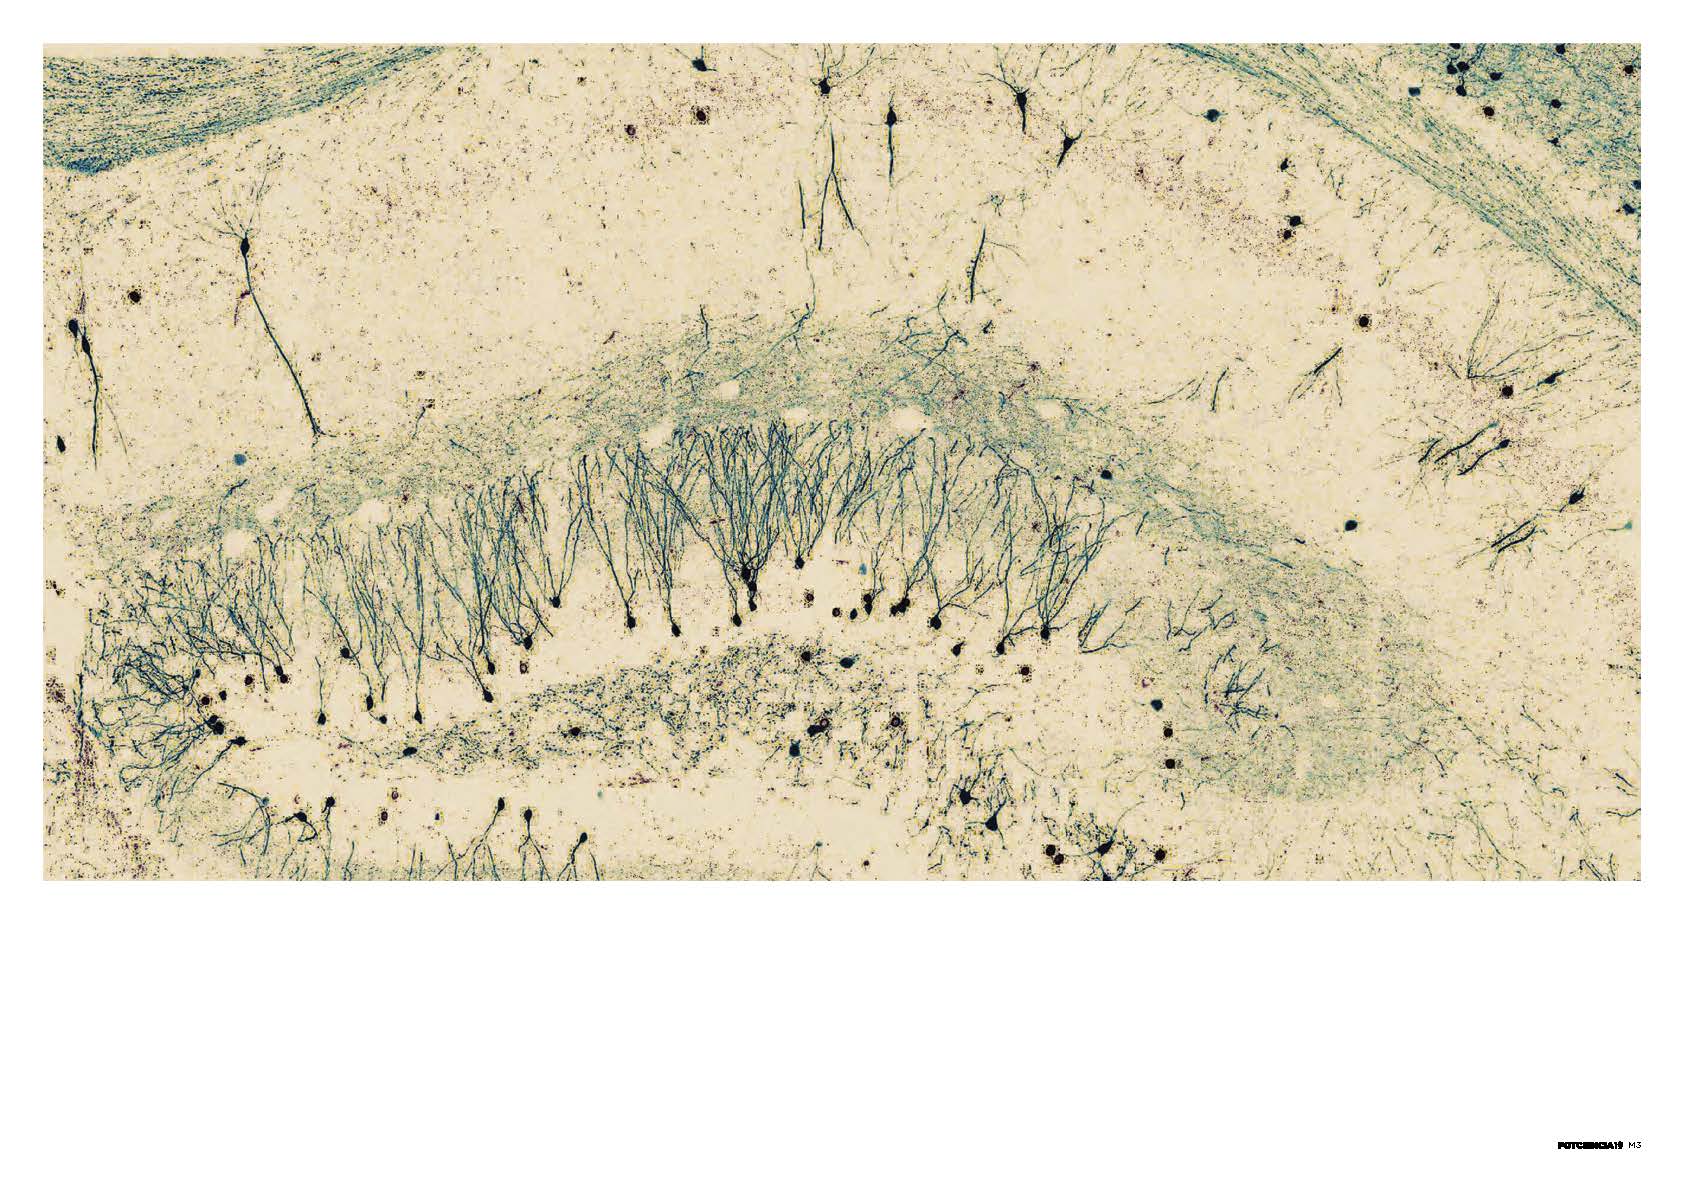

En su 19ª edición, FOTCIENCIA ha incluido una modalidad especial con motivo del Año Cajal, con imágenes relacionadas con las neurociencias.